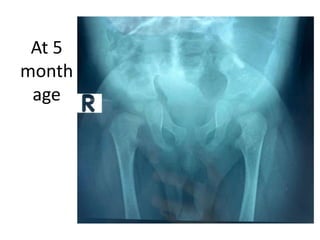

Phase-3: 2 marks

If the candidate orders some

investigations such as X-Ray show

him the X-Ray (and not the report)

and ask him:

1. What do you find on X-

Ray?

2. How will you proceed

further?

If the candidate reads X-Ray

correctly, draw referral lines and

request additional imaging show him

and ask why

CT / MRI

At 5

month

age

Phase-3: 2 marks Ifthe candidate orders some investigations such as X-Ray show him the X-Ray (and not the report) and ask him: 1. What do you find on X- Ray? 2. How will you proceed further? If the candidate reads X-Ray correctly, draw referral lines and request additional imaging show him and ask why CT / MRI